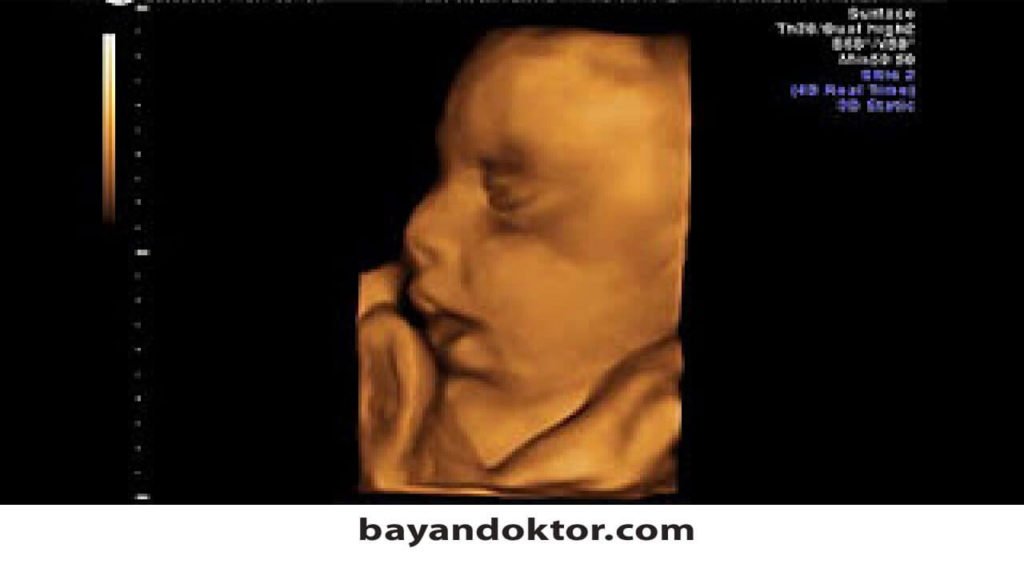

25 haftalık bebek ultrasonda anne karnında nasıl görünür?

Haftasında anne karnı hamileliğini yansıtacak derecede şişmiş bir büyüklüğe ulaşmıştır. 25 haftalık bebeğin anne karnındaki gelişiminin büyük kısmı tamamlanmıştır. 25 haftalık hamilelikte fetüsün gelişimi ile ilgili olarak, bebeğin saçlarının ortaya çıktığı ve doğumdan sonra değişebilmesine rağmen tanımlanmış bir. Kollar ve bacaklar kadar el ve ayak parmaklarını da hareket ettirmekten hoşlanır. Gebelikte 25 hafta 3d ve 4 boyutlu ultrason görüntüsü. Haftasında annede meydana gelen değişiklikler hamilelikte hemeroid.

Gebelikte 25 hafta 3d ve 4 boyutlu ultrason görüntüsü. Yirmi beşinci hafta civarında bebeğin omurilik (vertebra) yapıları kemik, eklem ve bağlarıyla şekillenmeye başlar. Kollar ve bacaklar kadar el ve ayak parmaklarını da hareket ettirmekten hoşlanır.

Söz konusu böylesine hızlı bir değişim içinde olan bebeğiniz ve bedeniniz olunca, 25 haftalık bebek görüntüsü en çok merak edilen konuların da başında gelir. 25 haftalık ultrason görüntüsü bebek bu günlerde güçlü bir şekilde hareket eder ve bebeğin sağlıklı olduğunu ve rahim içinde iyi olduğunu gösteren bir uyku düzenini takip eder. 25 haftalık hamilelikte fetüsün gelişimi.

Hafta hamilelikte ultrason görüntüsü aşağıdaki gibidir. Hamileliğin yirmi beşinci haftası / “bana hazır mısın?” 25 haftalık gebelik döneminin en önemli olayı, bebeğinizin tat duyusunun büyük ölçüde gelişmiş olması.tat duyusu ile birlikte ister inanın ister. 25 haftalık gebelikte bebek ağırlığı 650 gram, bebeğin boyu ise 34 cm civarındadır.

25 haftalık bebek ultrasonda anne karnında nasıl görünür? Kollar ve bacaklar kadar el ve ayak parmaklarını da hareket ettirmekten hoşlanır. 25 haftalık bebek ultrason görüntüsü izlendiğinde ellerinin yumruk olduğu ya da parmaklarını emme anı izlenebilir.

25 haftalık hamilelikte fetüsün gelişimi. 25 haftalık ultrason görüntüsü bebek bu günlerde güçlü bir şekilde hareket eder ve bebeğin sağlıklı olduğunu ve rahim içinde iyi olduğunu gösteren bir uyku düzenini takip eder. Hafta bebek gelişimi ayrıntılı ultrason.

Rahmin yukarı ve dışarı doğru çıkması, bebeğin kilo alması ile birlikte anne karnı belirginleşecek büyüklüğe gelebilir. 25 haftalık bebek ultrason görüntüsü izlendiğinde ellerinin yumruk olduğu ya da parmaklarını emme anı izlenebilir. 25 haftalık hamilelikte fetüsün gelişimi.